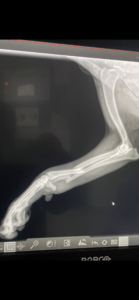

Sierra’s broken leg